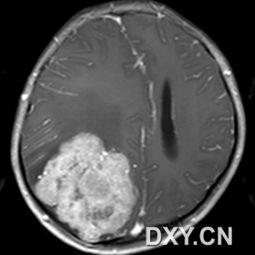

2. MRI扫描:MRI扫描可以提供更详细的图像,有助于判断肿瘤的性质和周围组织的受累情况。

接下来,让我们一起来解读一下这些脑肿瘤图片。

1. 肿瘤的形态:良性肿瘤通常呈圆形或椭圆形,边界清晰;而恶性肿瘤则形态不规则,边界模糊。

2. 肿瘤的大小:肿瘤的大小可以反映其生长速度和恶性程度。

3. 肿瘤的位置:肿瘤的位置可以影响其症状和治疗效果。

4. 肿瘤的密度:肿瘤的密度可以反映其成分,有助于判断肿瘤的性质。